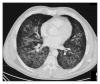

Image Diagnosis: Hemorrhagic Bullae in a Primary Varicella Zoster Virus Infection